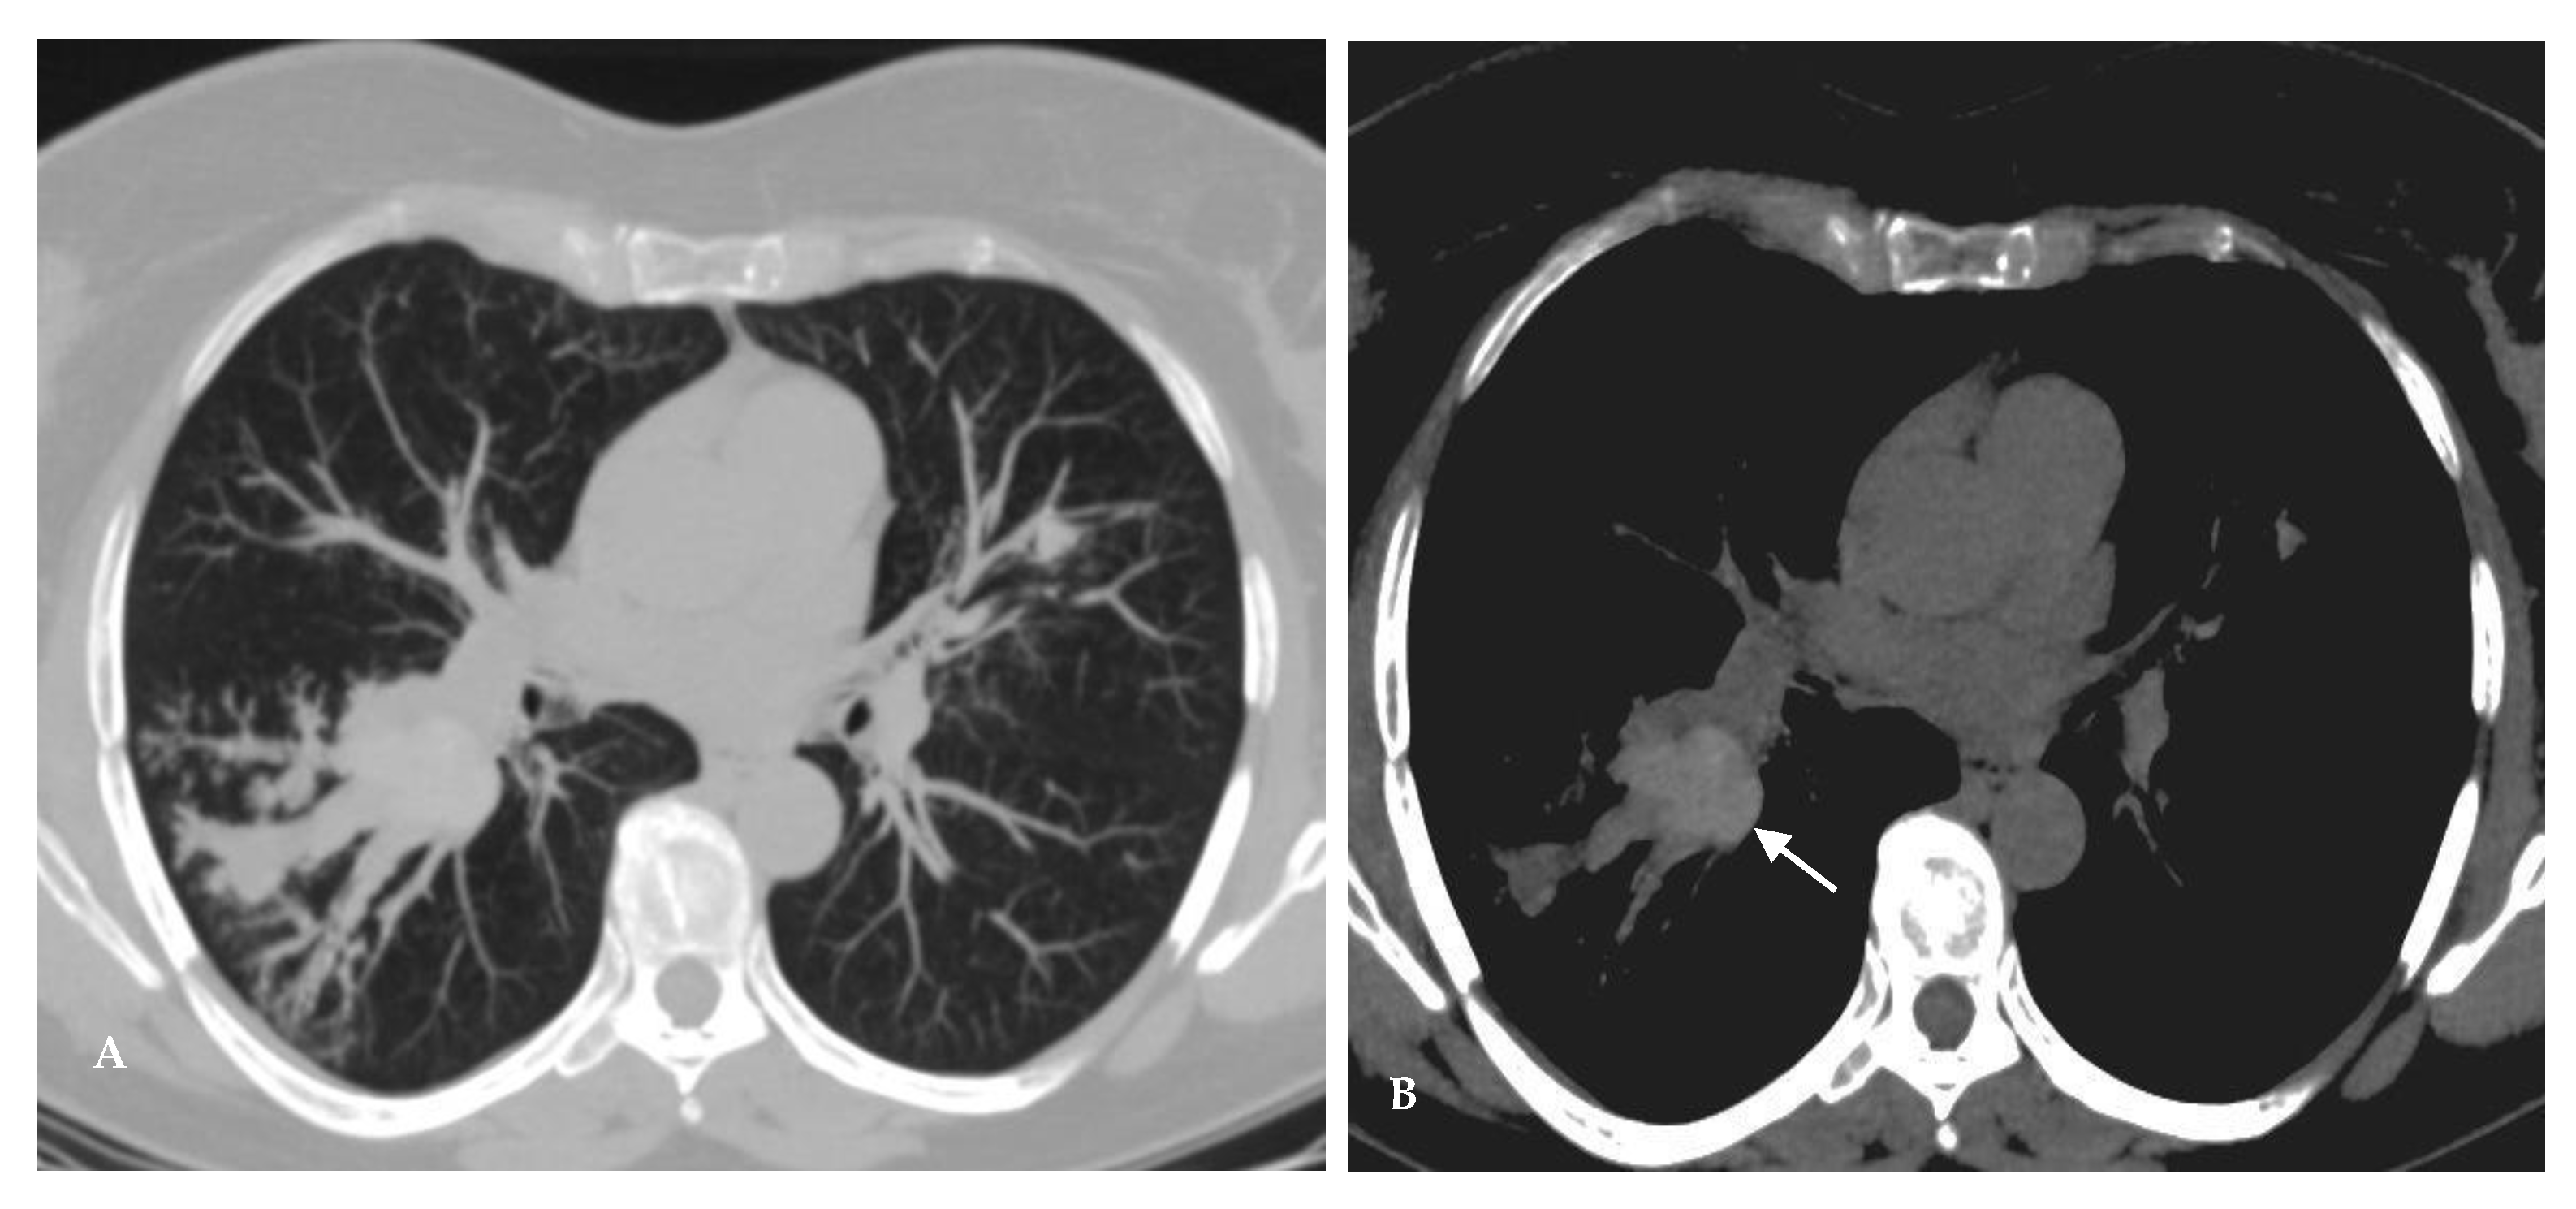

2.1. Lung Nodule or Mass

- Garrana, S.H.; Buckley, J.R.; Rosado-de-Christenson, M.L.; Martínez-Jiménez, S.; Muñoz, P.; Borsa, J.J. Multimodality Imaging of Focal and Diffuse Fibrosing Mediastinitis. Radiographics 2019, 39, 651–667. [Google Scholar] [CrossRef]